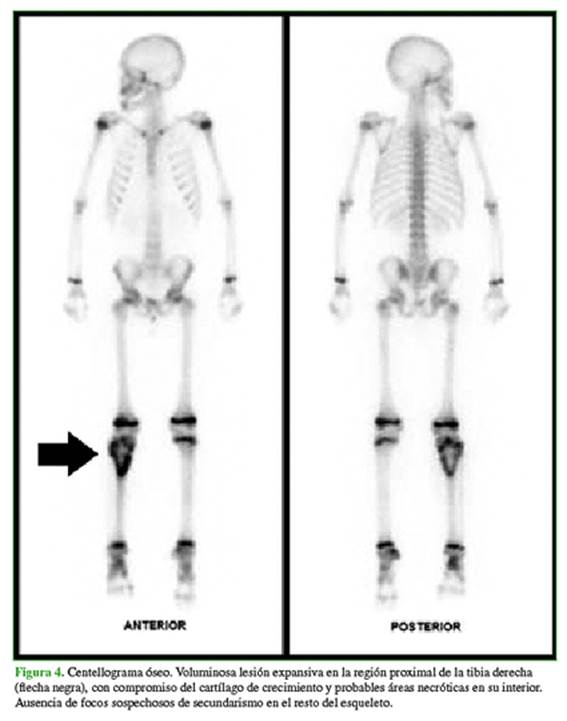

Se solicita un centellograma óseo (Figura 4) y una tomografía de tórax y abdomen para la estadificación (Figura 5).

Hallazgos en estudios de medicina nuclear

En la gammagrafía ósea, se puede visualizar una lesión única o lesiones en salto, en el mismo hueso o en el hueso adyacente. La tomografía por emisión de positrones sirve para la evaluación del pronóstico.